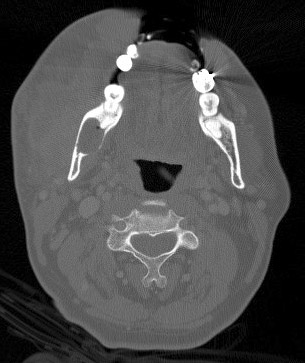

CT scan

Imaging:

• The panoramic view and the CT scan demonstrated a unlilocular, well demarcated, radiolucent lesion in the posterior aspect of the mandible. The rim of the lesion is smooth. There is no calcification at the center of the lesion.

• The mandible, particularly the posterior aspect, is more affected than the maxilla.

• Well-defined, round or ovoid unilocular ardiolucency with smooth margin and frequently associated with an unerupted tooth.